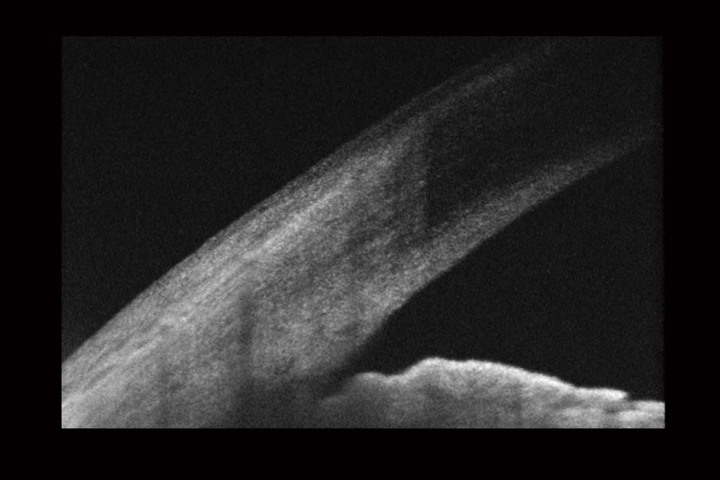

Optical Coherence Tomography uses low intensity infra-red light to give a 3D image of the back of the eye.  It shows not only the surface but also the depth of the structures.  It is similar to using ultrasound and creates an image not unlike an MRI or CT scan.

A 3D section of the layers ofthe retina and vitreous jellyA 3D section of the layers of the retina and vitreous jellyAge-related Macular Degeneration Dry FormAge-related Macular Degeneration Dry FormAge-related Macular Degeneration Wet FormAge-related Macular Degeneration Wet FormThe vitreous (jelly) pulling on the retinaThe vitreous (jelly) pulling on the retinaImage of Retina (back of the eye)Image of Retina (back of the eye)